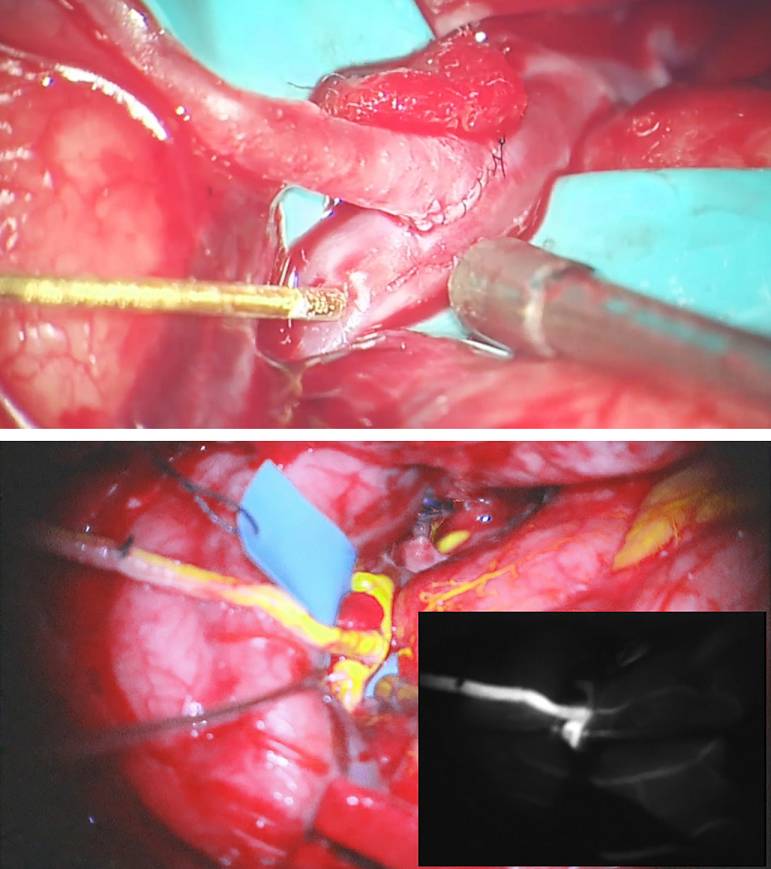

图5. 术区彻底止血。在受血动脉下方垫入一块带颜色的对照物(橡胶垫片)映衬透明的血管管壁,同时保护深面的脑组织。术中需要肝素盐水不断冲洗术区,在橡胶垫片下方留置一根具有持续吸引作用的引流管可以使吻合部位保持干燥。

随后,无菌油墨笔标记动脉管壁切开的位置。修整桥血管开口宽的一端并去除外膜,准备吻合。如果是大隐静脉,将断端宽的这侧吻合至受血动脉,可避免损伤静脉瓣膜,同时保持管腔内的血流方向。

临时阻断受血动脉(一般是M2)前,静脉使用2000-3000U的肝素。FiO2上调至100%,稍微升高血压促进侧支循环,并使用依托咪酯诱导爆发-抑制波形。尽量将临时阻断的时间控制在30-40min以下,但对于ECA-PCA这类技术难度大的搭桥,阻断时长往往会超过。

图6. 选取靠近MCA分叉部且没有分支的M2接受搭桥,小阻断夹中断其血流,然后,显微刀切开管壁并用显微剪沿标记线延长。

受血动脉造口的长度约为其管径的2-3倍。“鱼嘴样”扩大桥血管的远心端开口。采用间断缝合方式,以8-0或9-0的尼龙线吻合M2或P2端,以7-0的尼龙线吻合近端ICA。先在造口两极各缝合一针以对位、固定桥血管。

余下的漏口可以间断或连续缝合。结扎最后一针之前,再次用肝素盐水冲洗管腔。吻合完成后,在桥血管远离吻合口的部位放置一枚临时阻断夹,移除受血动脉的夹子使血流再通,以免阻断时间延长。吻合部位的出血/渗血可用止血纱和明胶海绵控制。

图7. 分别先在造口两极各穿入一针连续缝线以对位、固定桥血管(上图)。将桥血管翻向一侧便于完成侧壁的吻合。打结之前抽紧每根缝线(下图)。